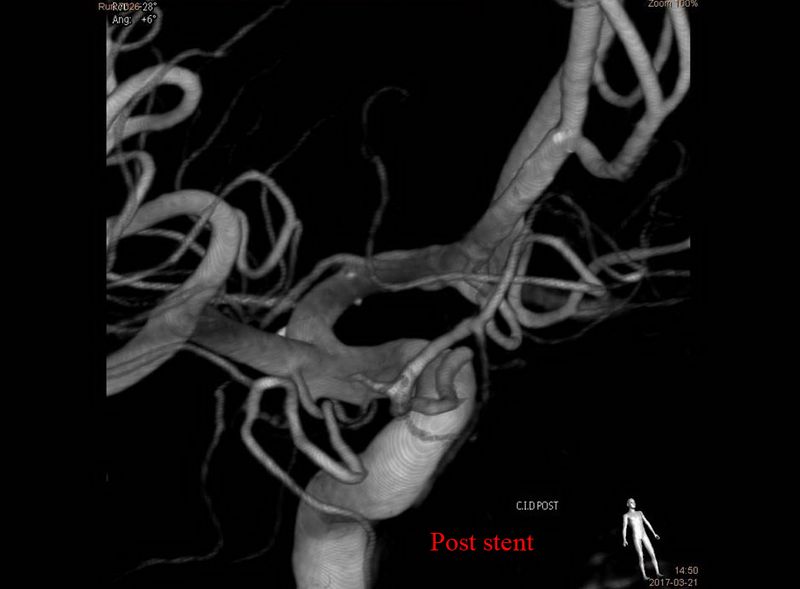

Aneurisma de arteria comunicante anterior